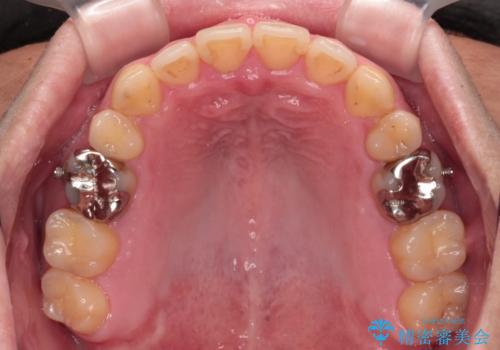

- 抜歯矯正の後戻りを気にして来院された患者様です。

舌の突出癖によるオープンバイトになり、前歯の叢生が後戻りしていました。

舌のトレーニングを行いながら、インビザラインを用いて矯正治療を行うこととしました。

インビザラインの特性を活用して奥歯の咬み合わせを圧下させることで、前歯のオープンバイトを改善さえることができました。